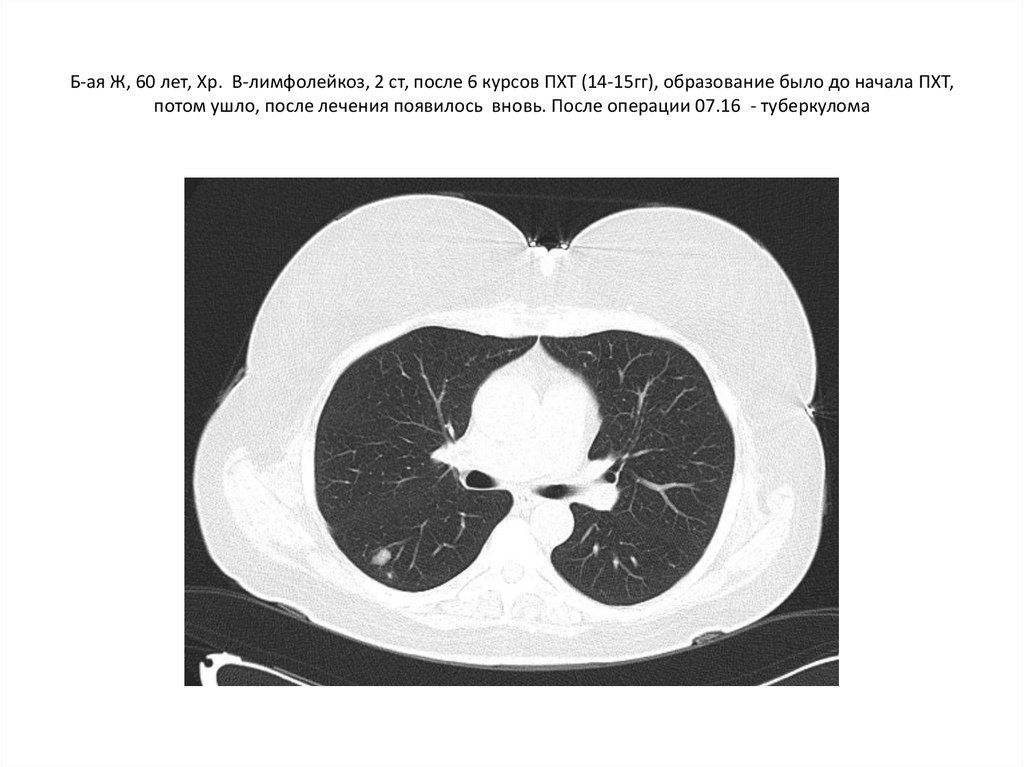

9. Б-ая Ж, 60 лет, Хр. В-лимфолейкоз, 2 ст, после 6 курсов ПХТ (14-15гг), образование было до начала ПХТ, потом ушло, после

лечения появилось вновь. После операции 07.16 - туберкулома